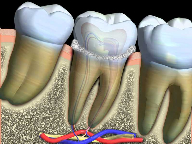

Recurrent decay (decay around existing fillings) can be detected during recall exams. If left untreated, the decay will spread underneath the filling and the tooth may require extensive treatment.